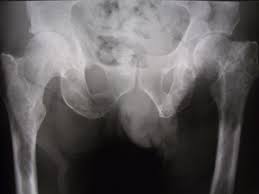

There may be other symptoms of bone cancer that may occur other than pain, however. Find out about the symptoms, causes, and treatment of chondrosarcoma, a type of bone cancer most common in your pelvis, thighbone, or upper arm. Bone metastasis can occur in any bone but more commonly occurs in the spine, pelvis and thigh. Bone metastasis may be the first sign that you have cancer, or bone. In contrast, some other metastatic tumors, such as those from the prostate, are commonly osteoblastic, meaning that they form new bone and increase the brittleness of the bones.

A high temperature (fever) of 38c (100.4f) or above It can spread to distant organs, such as the lungs. Bone cancer is rare, making up less than 1 percent of all cancers. Pelvic bone neoplasms are seldom immediately diagnosed and, therefore, may result in significant morbidity and mortality. Osteosarcoma is probably the most common disease that is related to pelvic bone cancer, with chondrosarcoma following close behind it. Hip pain is a common complaint like that of knee or back pain. At first, the pain is not constant. Bone metastases can weaken your bones and lead to symptoms like bone pain. The bones are the most common place where metastatic breast cancer cells tend to go. Chondrosarcoma is a cancer that can begin in the bones or tissue near bones, often in the hip, pelvis, and shoulder. Symptoms of testicular cancer may include: Can bone cancer be found early? Having too much calcium in your blood , which has numerous causes, is a dangerous condition called.

The bones are the most common place where metastatic breast cancer cells tend to go. A person may, for example, have lumps in the pelvic region or experience pain in the area. Learn more about the symptoms, risk factors, diagnosis, types, treatment, and outlook for bone cancer. Your red blood cell levels may drop, causing anemia. Pain, fever, and fatigue are all symptoms associated with pelvic bone cancer. Chondrosarcoma is a rare type of cancer that usually begins in the bones, but can sometimes occur in the soft tissue near bones. There's no cure for metastatic bone cancer, but treatment options may help alleviate symptoms to keep you comfortable. Pain and swelling in the. At first, the pain is not constant. Metastatic tumors of the bones are usually osteolytic, which means that they dissolve the bone and cause multiple fractures. Abstract low back pain and sciatica are usually attributed to localized structural pathology; The long bones of the body — such as the arms and legs — and the pelvis are commonly affected. Symptoms if cancer has spread to the lymph nodes lymph nodes are part of a system of tubes and glands in the body that filters body fluids and fights infection.